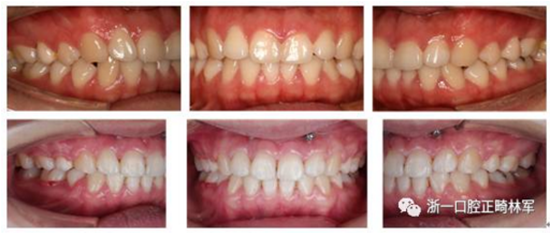

我們給她拔了4顆牙第一前磨牙,打了骨釘,來排齊牙齒,內(nèi)收前牙,改善側(cè)貌,后期又做了牙齦小手術(shù),幫她把露齦笑也解決了,最后治療結(jié)束時她不僅牙齒整齊、咬合良好,而且側(cè)貌漂亮,治療前嘴巴前突、下巴后縮、露齦笑的問題都改善了,她對此很滿意。一起來看看效果吧!

治療前后面像、口內(nèi)像對比

8.png

9.png

10.png